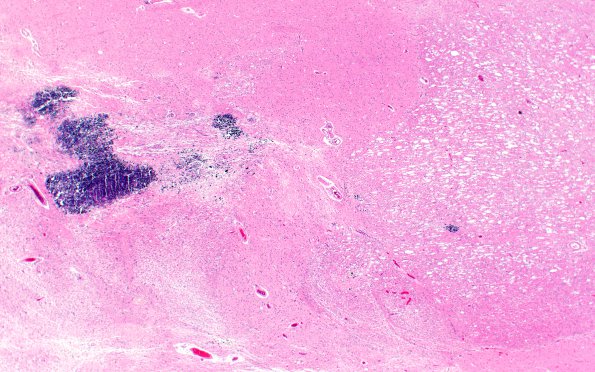

Washington University Experience | MYELIN (NON-IMMUNE MEDIATED) | Retinal Vasculopathy with Cerebral Leukoencephalopathy (RVCL, TREX1 Mutation) | 17C3 RVCL (Case 17) N13 H&E 2X

17C3-5 Higher magnification examination shows calcifications, myelin pallor, astrocytosis, necrosis and angiopathy. (H&E)